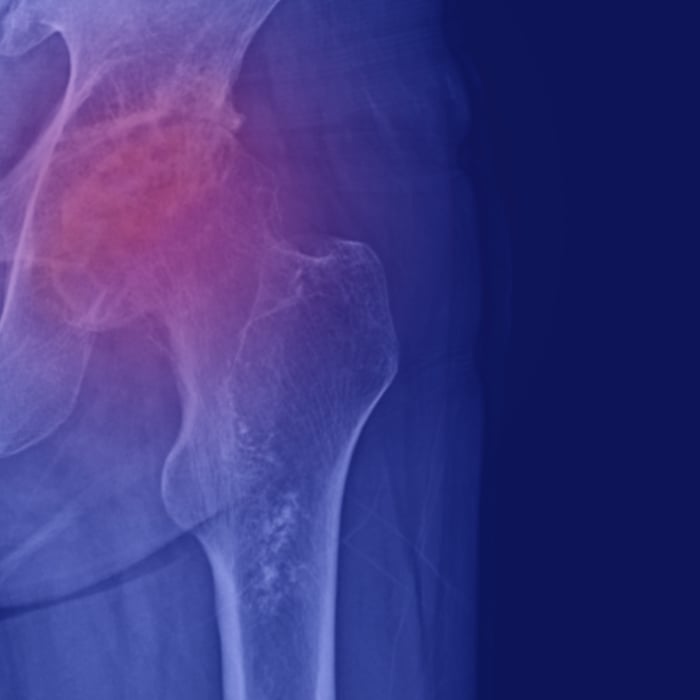

Avascular necrosis (AVN), also known as aseptic osteonecrosis, occurs when blood flow to a bone is disrupted, leading to oxygen deprivation and the eventual death of bone tissue. The most commonly affected site is the femoral head, though AVN can also involve the femoral condyles, humeral head, talus, calcaneus, or navicular bones.

At Hyperbaric Medical Solutions, under the guidance of Dr. Alan Katz, AVN is viewed not just as structural bone failure but as a metabolic, oxygen-deprivation disease. When oxygen levels drop, bone cells lose vitality, inflammation increases, and tissue repair halts—causing pain, stiffness, and progressive loss of joint function.

Avascular necrosis occurs when blood supply to bone tissue is reduced or interrupted. Without sufficient oxygen delivery, bone cells fail to maintain structural integrity, leading to progressive tissue compromise. Early AVN is a metabolic failure, not merely a structural issue.

Once structural collapse begins, regenerative options become limited. HBOT is most effective when introduced before significant bone deformation occurs, allowing oxygen-driven repair mechanisms to stabilize the femoral head and preserve joint function.

Hyperbaric oxygen therapy (HBOT) increases plasma oxygen concentration, enabling oxygen to reach areas of compromised circulation within the femoral head.

By improving tissue oxygenation, HBOT helps maintain bone cell viability, stimulates angiogenesis, and may reduce intraosseous pressure. These effects form the foundation of the preservation-first approach used at Hyperbaric Medical Solutions.